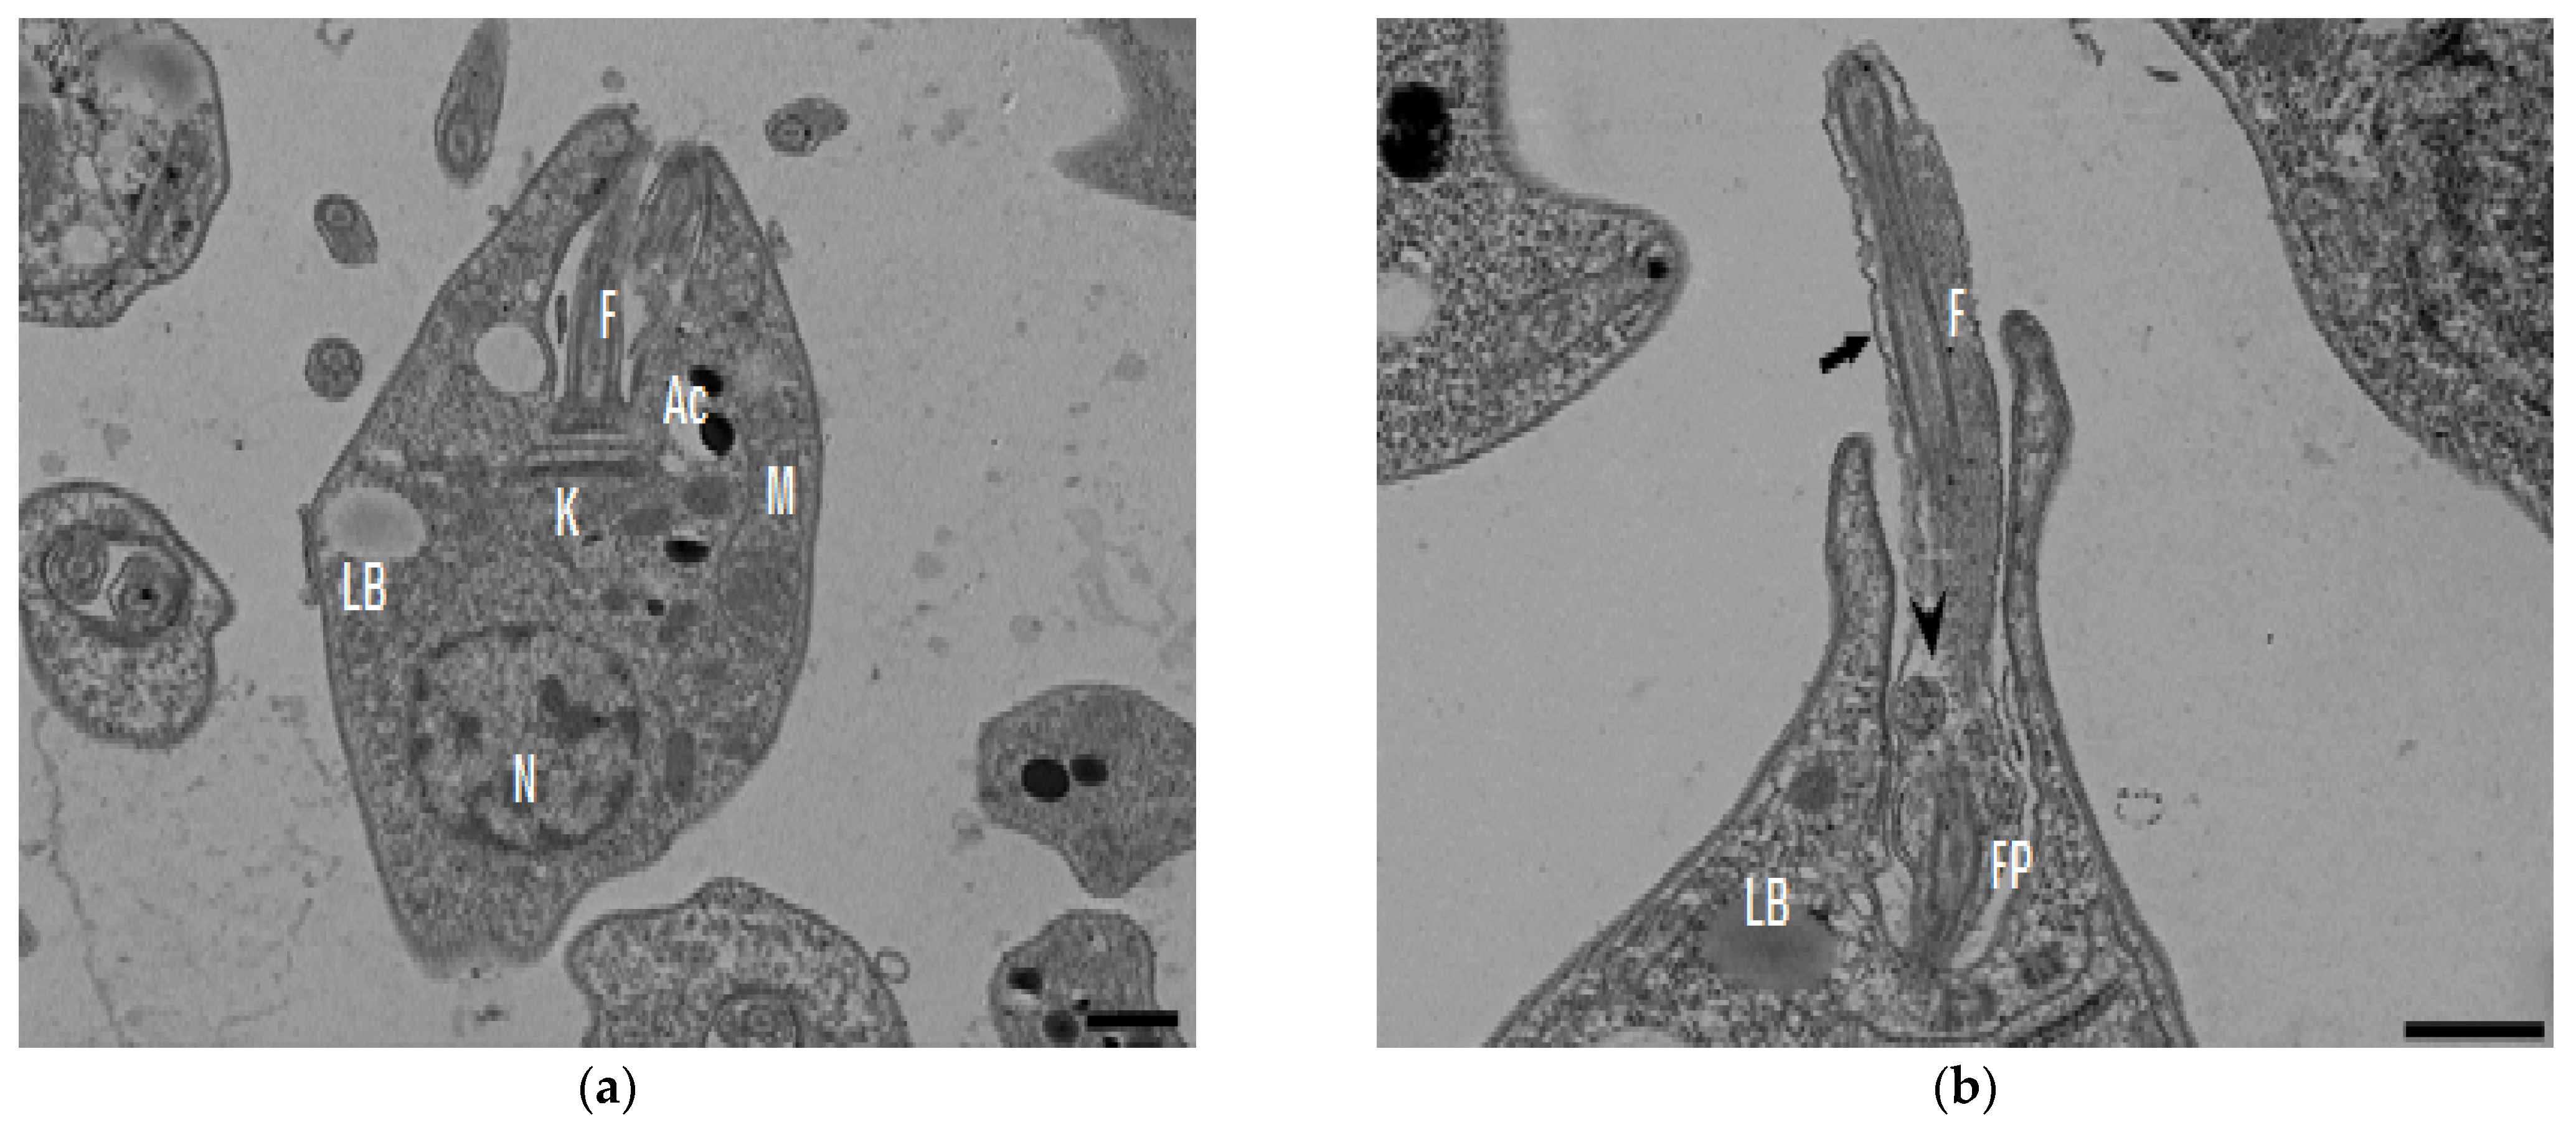

In the TEM studies (Figure 2), the control parasites were found to have plasma membranes and their characteristic structures without any damage (Figure 2a). However, the parasites treated for 6 h at 0.32 µM showed some early effects induced by compound 8 (Figure 2b–d). Some ultrastructural changes were evident such as the formation of autophagosomes and mitochondrion swelling with the presence of concentric membranal structures inside as well as an exocytic activity in the flagellar pocket, detachment of the flagellar membrane and alterations in the kinetoplast. Meanwhile, at 3.2 µM for 12 h (Figure 2e–h), the treated parasites showed even more profound changes such as the presence of increased vacuolization and autophagosomes, cytoplasmic myelin-like figures, plasma membrane detachment, rupture of the nuclear membrane and abnormal chromatin condensation. Total mitochondrion disorganization with swelling and concentrical membranes inside and, in some cases, the loss of cell integrity and cytosolic content were also observed.

Figure 2.

TEM analysis of L. mexicana promastigotes: non-treated (a) and treated with compound 8 at 0.32 µM 6 h (b–d) and 3.2 µM for 12 h (e–h). Control parasites show a normal morphology. Parasites treated with compound 8 show the presence of autophagosomes (APs) (d,f,h) and several alterations such as flagellar membrane detachment (black arrow) and exocytic activity in the flagellar pocket (black arrowhead) (b), kinetoplast structural alterations (c), mitochondrion swelling and concentric membranes inside (asterisks) (d,f,g), chromatin condensation (white arrowhead) (c,e,g,h), rupture of nuclear membrane (white arrow) (c,g,h), plasmatic membrane detachment (black arrow) (e) and cytoplasmic myelin figures (white stars) (e,g); loss of cell integrity and cytosolic content (white rhombus) (e,f); nucleus (N), mitochondrion (M), flagella (F), flagellar pocket (FP), kinetoplast (K), acidocalcisome (Ac), lipid body (LB), vacuole (V) (bar = 0.5 µm).

In the present study, with an interest in continuing the characterization of compound 8’s leishmanicidal activity, SEM studies were performed. It was demonstrated that compound 8 induced important ultrastructural changes in L. mexicana promastigotes such as membrane blebbing resembling an apoptotic-like process [20] and alterations in the flagella structure. In addition, TEM studies revealed alterations in the kinetoplast structure and profound mitochondrion damage including swelling and the presence of concentric membranes inside the organelle. We also observed cytoplasmic myelin-like figures indicative of an autophagy process, among other changes. Similar findings were described when L. amazonensis promastigotes were treated with Miltefosine [20], antifungal azoles [21] and calpains inhibitors [22]. In trypanosomastids, severe mitochondrion damage as well as an intense autophagy process and subsequent apoptosis cell death was related to a significant increase in reactive oxygen and nitrogen species (ROS and RNS) [23]. Parasites are exposed to extracellular ROS during their entire life cycle in the insect vector, as well as during the invasion of mammalian host cells [24], but ROS are also produced within the parasite through its electron transport chain or drug detoxification. In the present study, it was demonstrated that compound 8 triggers the production of ROS and parasite apoptosis, indicating that intracellular ROS production induced with compound 8 could be related to mitochondrial damage, as well as membrane blebbing and myelin-like figures observed in the SEM and TEM studies. Parasite apoptosis induced with compound 8 was demonstrated in the flow cytometry studies.